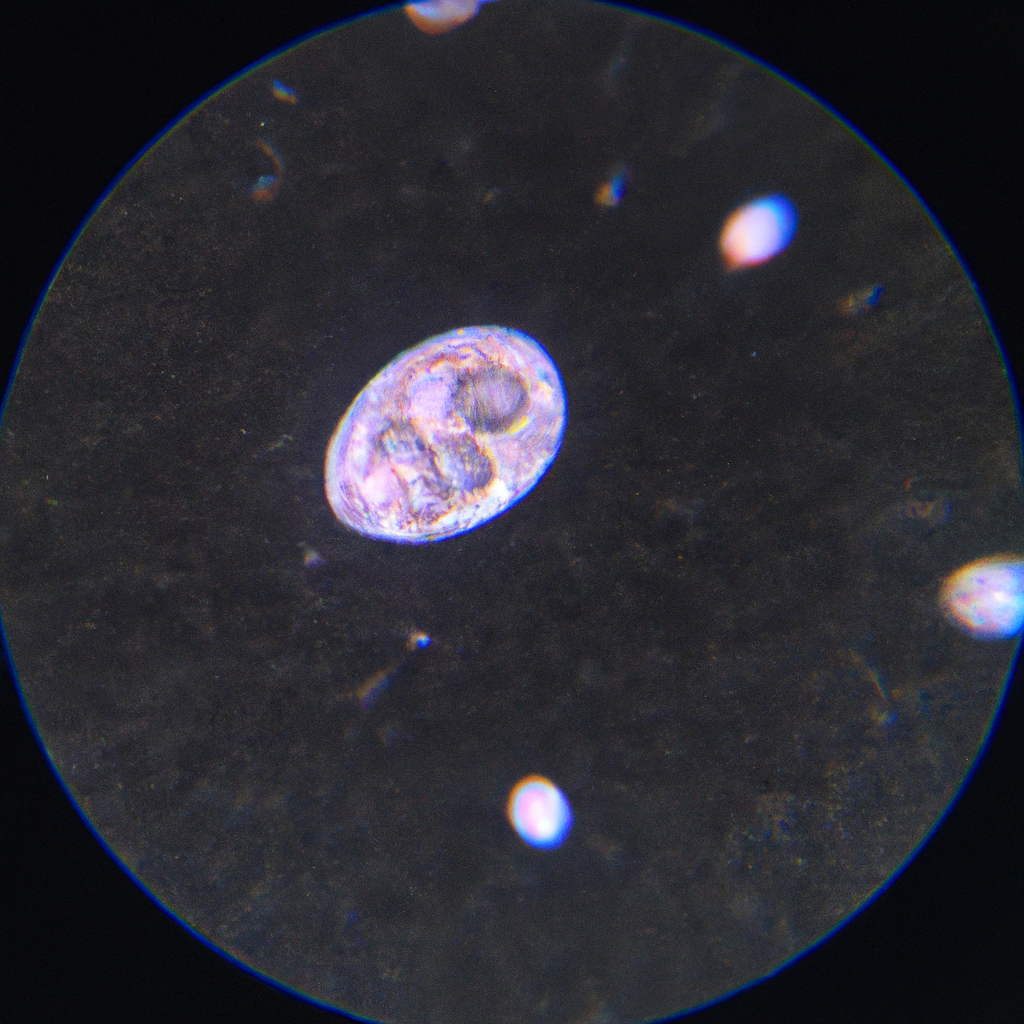

Gambar Proses Ovulasi

Saat level estrogen mencapai puncaknya, ovarium akan merespon dengan melepaskan hormon Luteinizing Hormone (LH). Hormon LH inilah yang akan memicu ovulasi, di mana sel telur yang sudah matang akan dilepaskan dari ovarium dan masuk ke dalam saluran telur. Sel telur yang dilepaskan ini memiliki umur berkisar antara 12-24 jam dan jika tidak dibuahi oleh sperma, maka sel telur ini akan terbuang bersama dengan jaringan rahim saat menstruasi berlangsung.